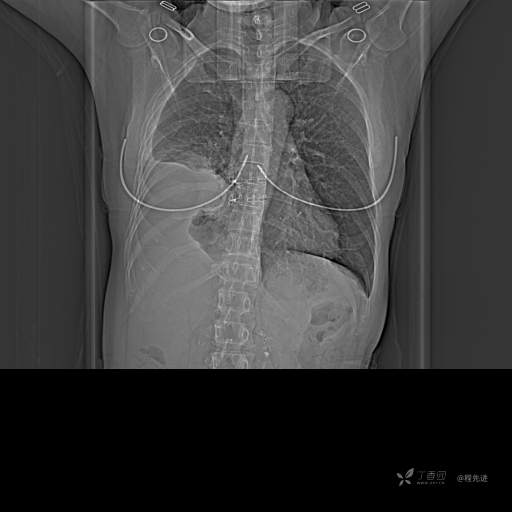

患者性别:女

患者年龄:51岁

简要病史:胸闷半年